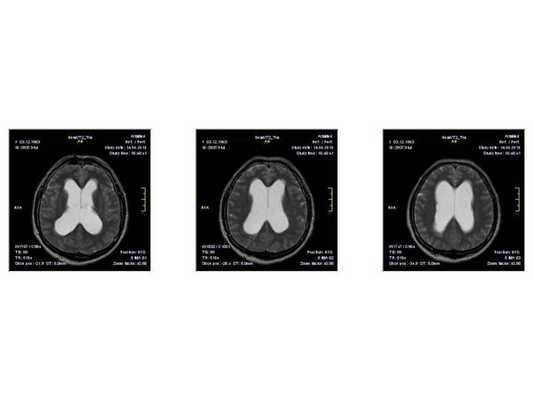

МР-томограмма нормального головного мозга. Серым цветом изображено вещество мозга, белым - ликвор. Нормальная величина жидкостных пространств головного мозга (они щелевидны). Желудочки видны внутри мозга. Субарахноидальные пространства - белая кайма вокруг мозга.

МР-томограммы при внутричерепной гипертензии и гидроцефалии. Результат недостаточного лечения повышенного внутричерепного давления. Видно избыточное скопление ликвора внутри головного мозга (в виде бабочки) и снаружи мозга (широкая белая кайма). Объем мозгового вещества уменьшен - атрофия головного мозга от давления жидкостью.

- Расширение жидкостных полостей головного мозга и разрежение мозгового вещества по краю желудочков мозга, ясно видимое при компьютерной рентгеновской томографии (КТ) или магнитно-резонансной томографии (МРТ);

- МРТ в динамике показывает постепенное сужение желудочковой системы на 2 мм. Для сравнения представлены снимки МРТ от 14.05.2013 и от 16.10.2014.